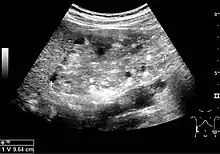

A solid renal mass appears in the US exam with internal echoes, without the well-defined, smooth walls seen in cysts, often with Doppler signal, and is frequently malignant or has a high malignant potential. The most common malignant renal parenchymal tumor is renal cell carcinoma (RCC), which accounts for 86% of the malignancies in the kidney. RCCs are typically isoechoic and peripherally located in the parenchyma, but can be both hypo- and hyper-echoic and are found centrally in medulla or sinus. The lesions can be multifocal and have cystic elements due to necrosis, calcifications and be multifocal (Figure 8 and Figure 9). RCC is associated with von Hippel–Lindau disease, and with tuberous sclerosis, and US has been recommended as a tool for assessment and follow-up of renal masses in these patients.[1]

However, US is not the primary modality for the evaluation of solid tumors in the kidney, and CT is the first choice modality. Nevertheless, hemorrhagic cysts can resemble RCC on CT, but they are easily distinguished with Doppler ultrasonography. In RCCs, Doppler US often shows vessels with high velocities caused by neovascularization and arteriovenous shunting. Some RCCs are hypovascular and not distinguishable with Doppler US. Therefore, renal tumors without a Doppler signal, which are not obvious simple cysts on US and CT, should be further investigated with CEUS, as CEUS is more sensitive than both Doppler US and CT for the detection of hypovascular tumors.[1]